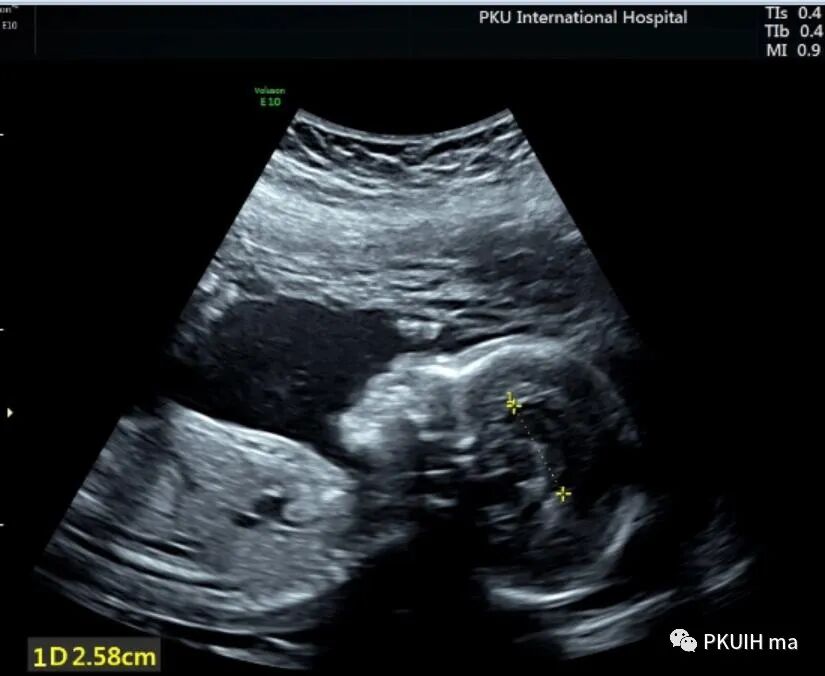

侧脑室看着也还可以没有发现有明显泪滴状,透明隔腔下方穹窿也存在,于是想着先看下胎儿胼胝体

透明隔腔是胎儿中枢神经系统正常发育的一个重要结构。其缺失或形态异常与许多中枢神经系统畸形有关。正常透明隔腔为位于脑中线前部两透明隔间的液体腔,其上方为胼胝体,下方为穹隆,侧壁为透明隔小叶。透明隔腔发育与胼胝体、前联合、穹隆柱密切相关。透明隔腔向后延伸至室间孔,室间孔后方为韦氏腔。

检查中不要把下方的穹窿柱和扩张上抬的三脑室以及融合的侧脑室前角误认为透明隔腔。正常情况下透明隔腔的内径约4-8mm,也有窄的或者宽的,只要形态正常即可,一般大于10mm可以报增宽,小于2mm考虑窄。此时需要关注透明隔腔的形态,一般透明隔腔呈长方形,个别的可以呈三角形,如果左右径大于前后径时认为形态异常。超声显示呈正方形或反长方形、圆形或者是前后径/左右径<1.5时要仔细观察胼胝体,以除外胼胝体发育异常。